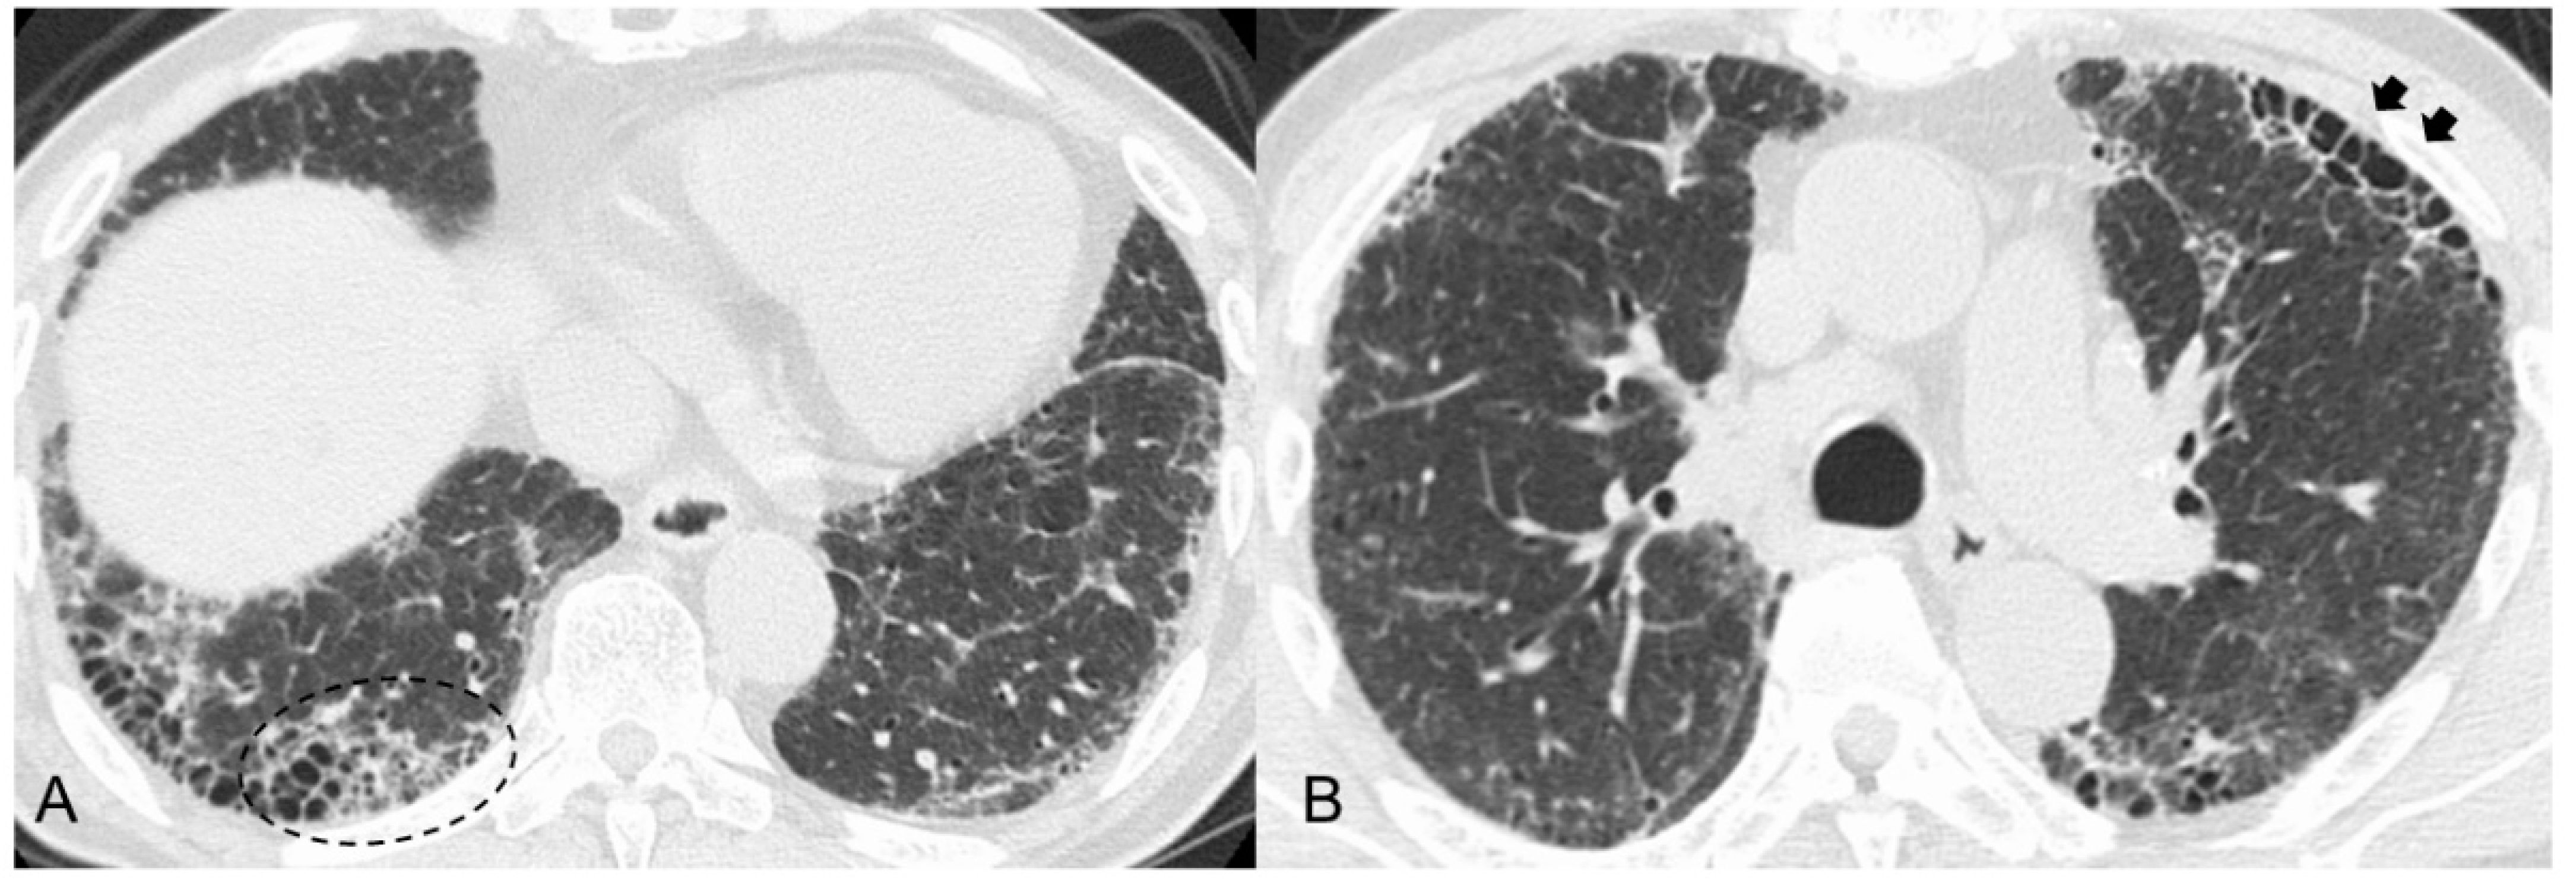

However, some previous studies reported that MPO-ANCA-positive ILD (including MPA-ILD) and UIP/IPF showed different radiopathological features, despite having the same basic UIP pattern [30,31,33,34,35]. Radiologically, increased attenuation around areas of honeycombing and traction bronchiectasis (Figure 1A) was more frequently seen in MPO-ANCA-positive ILD than in UIP/IPF [30,31,34]. We reported that an anterior upper lobe honeycomb-like lesion, which represents a concentration of cystic air spaces within the anterior aspect of the upper lobes (Figure 1B), might be found with higher frequency in MPO-ANCA-positive ILD and RA-ILD than in other etiologies associated with ILD [31,42]. Pathologically, MPO-ANCA-positive ILD even with a UIP pattern showed more prominent inflammatory cell infiltration and cellular bronchiolitis, unlike UIP/IPF (Figure 2A–E) [8,14,17,33,34,35]. In other words, these pathological features correspond well to the presence of a radiological feature such as increased attenuation around areas of honeycombing and traction bronchiectasis [30,31,34]. Therefore, these features may be associated with a better response to anti-inflammatory therapies in MPO-ANCA-positive ILD patients, and clinicians should be careful to note the development of MPA in patients having these features [31,34] (Table 1).

Figure 1.

(A) High-resolution computed tomography (HRCT) scan shows increased attenuation around honeycombing and traction bronchiectasis (dashed circle). (B) HRCT shows anterior upper lobe honeycomb-like lesion as a concentration of cystic air spaces within the anterior aspect of the upper lobes (black arrows).